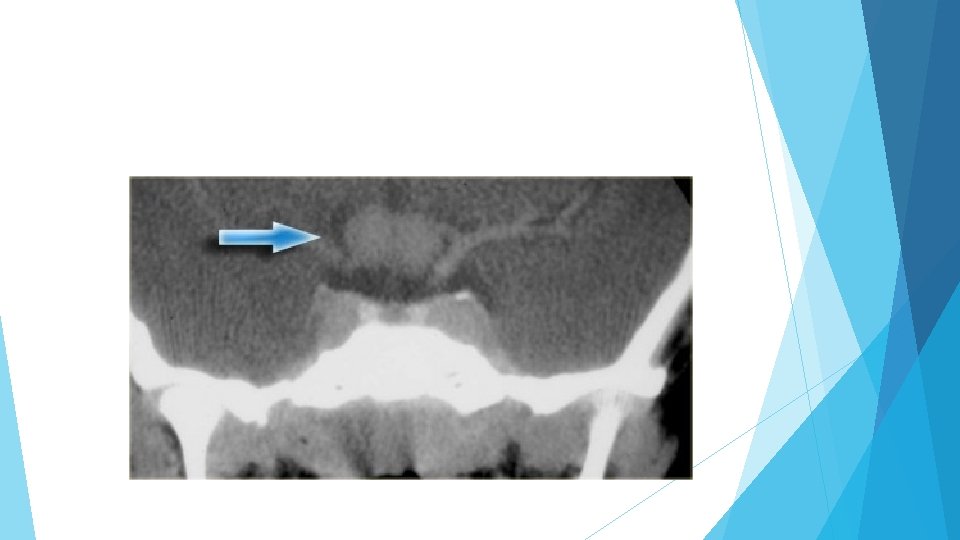

Chondromas are the most common lesions of the clivus, also a favored location for metastases and chondrosarcomas. A mass lesion posterior to normal pituitary gland. Some calcifications Chordomas tend to occur in the midline, whereas chondrosarcomas tend to occur off the midline.